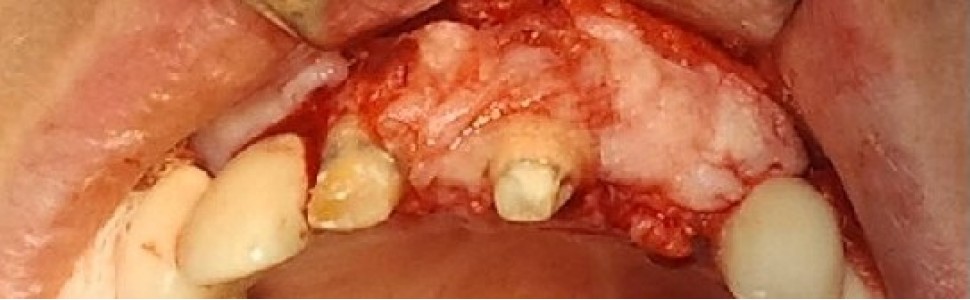

Bogata w płytki i leukocyty fibryna jest stosowana w regeneracji tkanek od ponad 15 lat. Pozytywny wpływ PRF (platelet-rich fibrin) na regenerację tkanek miękkich jest niewątpliwy, bezsporny i częściowo udowodniony w badaniach klinicznych i analizach biochemicznych. Wpływ PRF na regenerację tkanki kostnej jest obserwowany klinicznie, ale nadal niedostatecznie poznany jest mechanizm tego zjawiska.

Platelet- and leukocyte-rich-fibrin has been used in regeneration of tissue for more than 15 years. The positive influence of PRF on the regeneration of soft tissue is undoubtedly, without question and partially proven in clinical studies and biochemical analysis. Influence of PRF on regeneration of bone tissue is observed clinically but the mechanism of this phenomenon is still not sufficiently known.